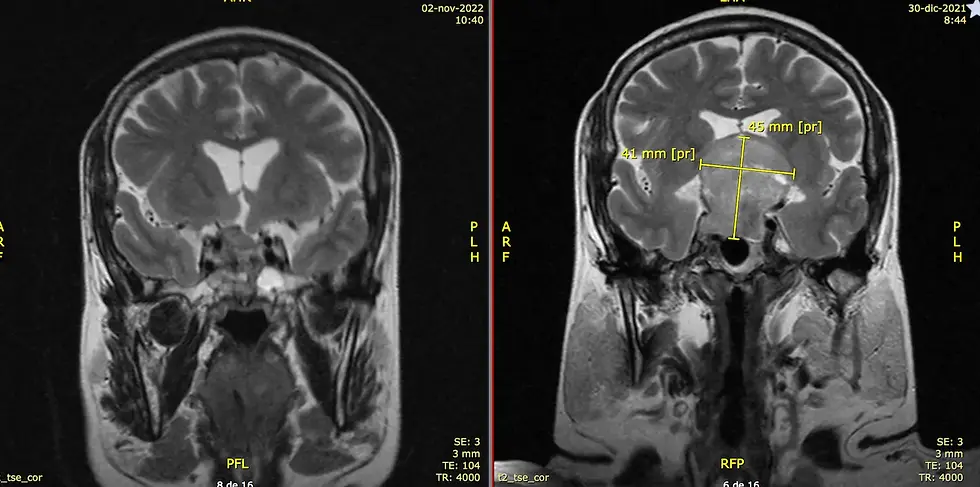

¿Cómo se diagnostica un tumor cerebral?

El diagnóstico suele implicar una combinación de estudios médicos que permiten identificar la localización, tamaño y características del tumor.

Entre los estudios más utilizados se encuentran:

resonancia magnética

tomografía computarizada

estudios neurológicos especializados

biopsia en algunos casos

Estos estudios ayudan a los especialistas a determinar el tipo de tumor y definir el tratamiento más adecuado.